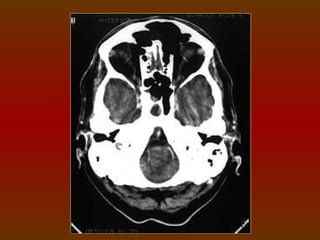

CORTE 1

a) Órbita (observe a elevada densidade do cristalino

na margem anterior do globo ocular)

b) Arco zigomático

c) Seio esfenoidal

d) Canal acústico externo

e) Processo mastóideo

f) Cerebelo

g) Protuberância occipital interna

h) Seios etmoidais

CORTE 1 a) Órbita(observe a elevada densidade do cristalino na margem anterior do globo ocular) b) Arco zigomático c) Seio esfenoidal d) Canal acústico externo e) Processo mastóideo f) Cerebelo g) Protuberância occipital interna h) Seios etmoidais